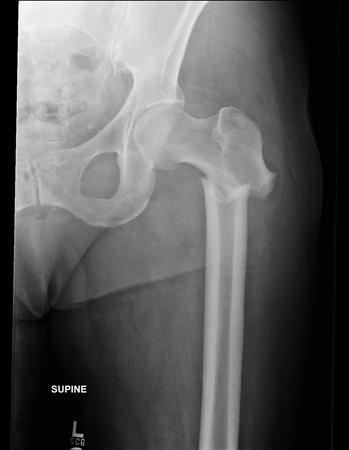

Subtrochanteric (proximal femur) fracture often occurs in

A

Osteoporotic bone in elderly

How well did you know this?

1

Not at all

2

3

4

5

Perfectly

6

Q

What are the issues with subtrochanteric fractures

It takes a long time to heal and Non-union often occurs due to poor blood supply to the area

7

Management of subtrochanteric fracture

1. Thomas splint for initial stabilisation

2. IM nail